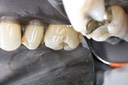

Wayne Chin #15 finish